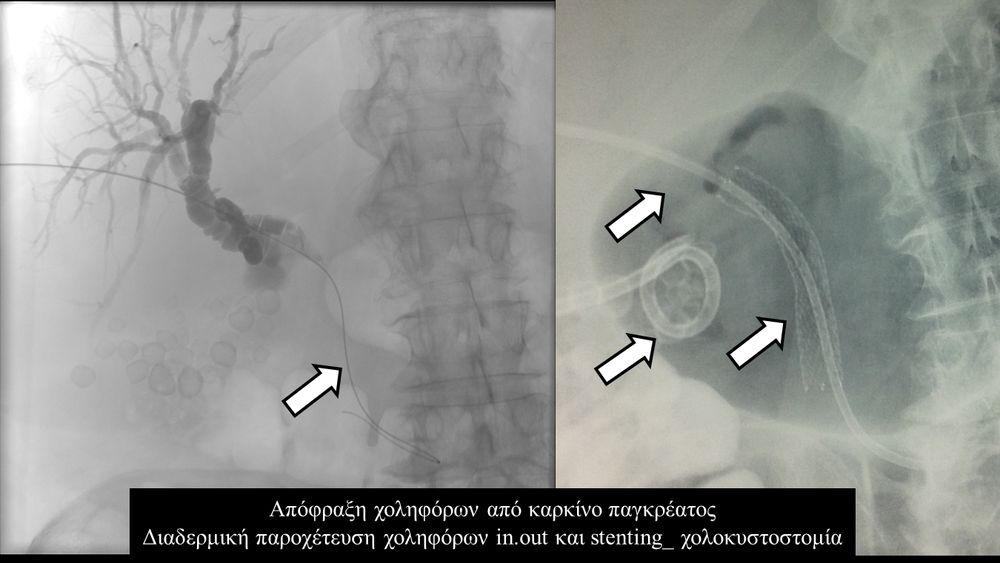

Σε πολλές περιπτώσεις πρωτοπαθών ή δευτεροπαθών όγκων ήπατος - παγκρέατος προκαλείται απόφραξη των χολαγγείων με συνοδό αποφρακτικό ίκτερο.Ο ασθενής με αποφρακτικό ίκτερο δεν μπορεί να υποβληθεί σε χημειοθεραπεία, αν δεν αποκατασταθεί ο ίκτερος με παροχέτευση των χοληφόρων.

Η παροχέτευση των χοληφόρων σε αυτές τις περιπτώσεις θα πρέπει να γίνεται άμεσα, είτε ταυτόχρονα προς τα έξω και προς το 12κτυλο (έσω-έξω παροχέτευση), είτε μόνο προς τα έξω με τη βοήθεια pigtailκαθετήρα (εξωτερική παροχέτευση)

Σε περιπτώσεις όπου υπάρχει απόφραξη των χοληφόρων και ενδείκνυται η τοποθέτηση ενδοπρόθεσης (stent), τότε η βατότητα των χολαγγείων και η αντιμετώπιση του αποφρακτικού ικτέρου μπορεί να διασφαλιστεί με την τοποθέτηση ενδοπροθέσεων (stents).